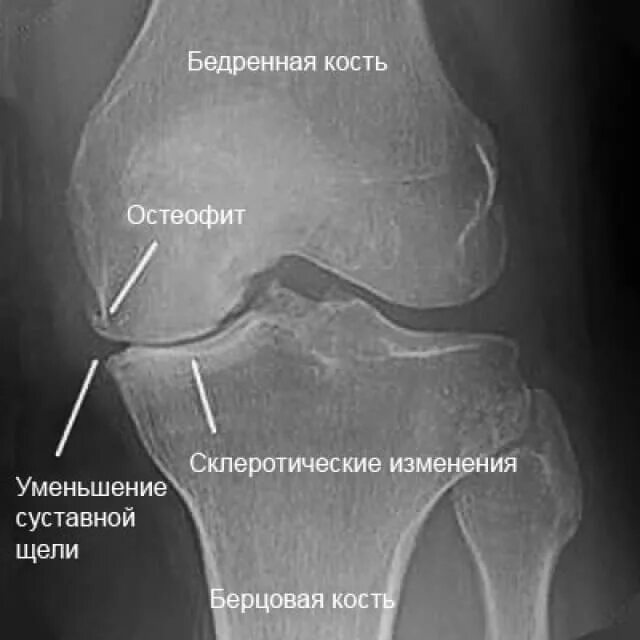

Лечение остеофитов сустав